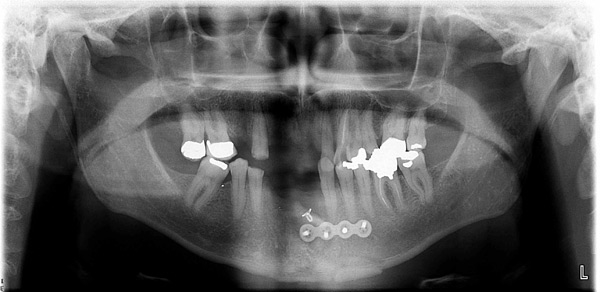

Case Study 3

Problem: This gentleman had an accident with a four-wheeler which gave him multiple jaw fractures and broken teeth. As a result of his accident, it left him with no teeth in the upper and lower front.

Plan: Our plan… the fractures were fixed and three implants were placed on the upper arch and two implants on the lower arch bridging the missing teeth. We also fixed a few broken teeth with root canals and crowns.

Don’t let accidents ruin your smile.